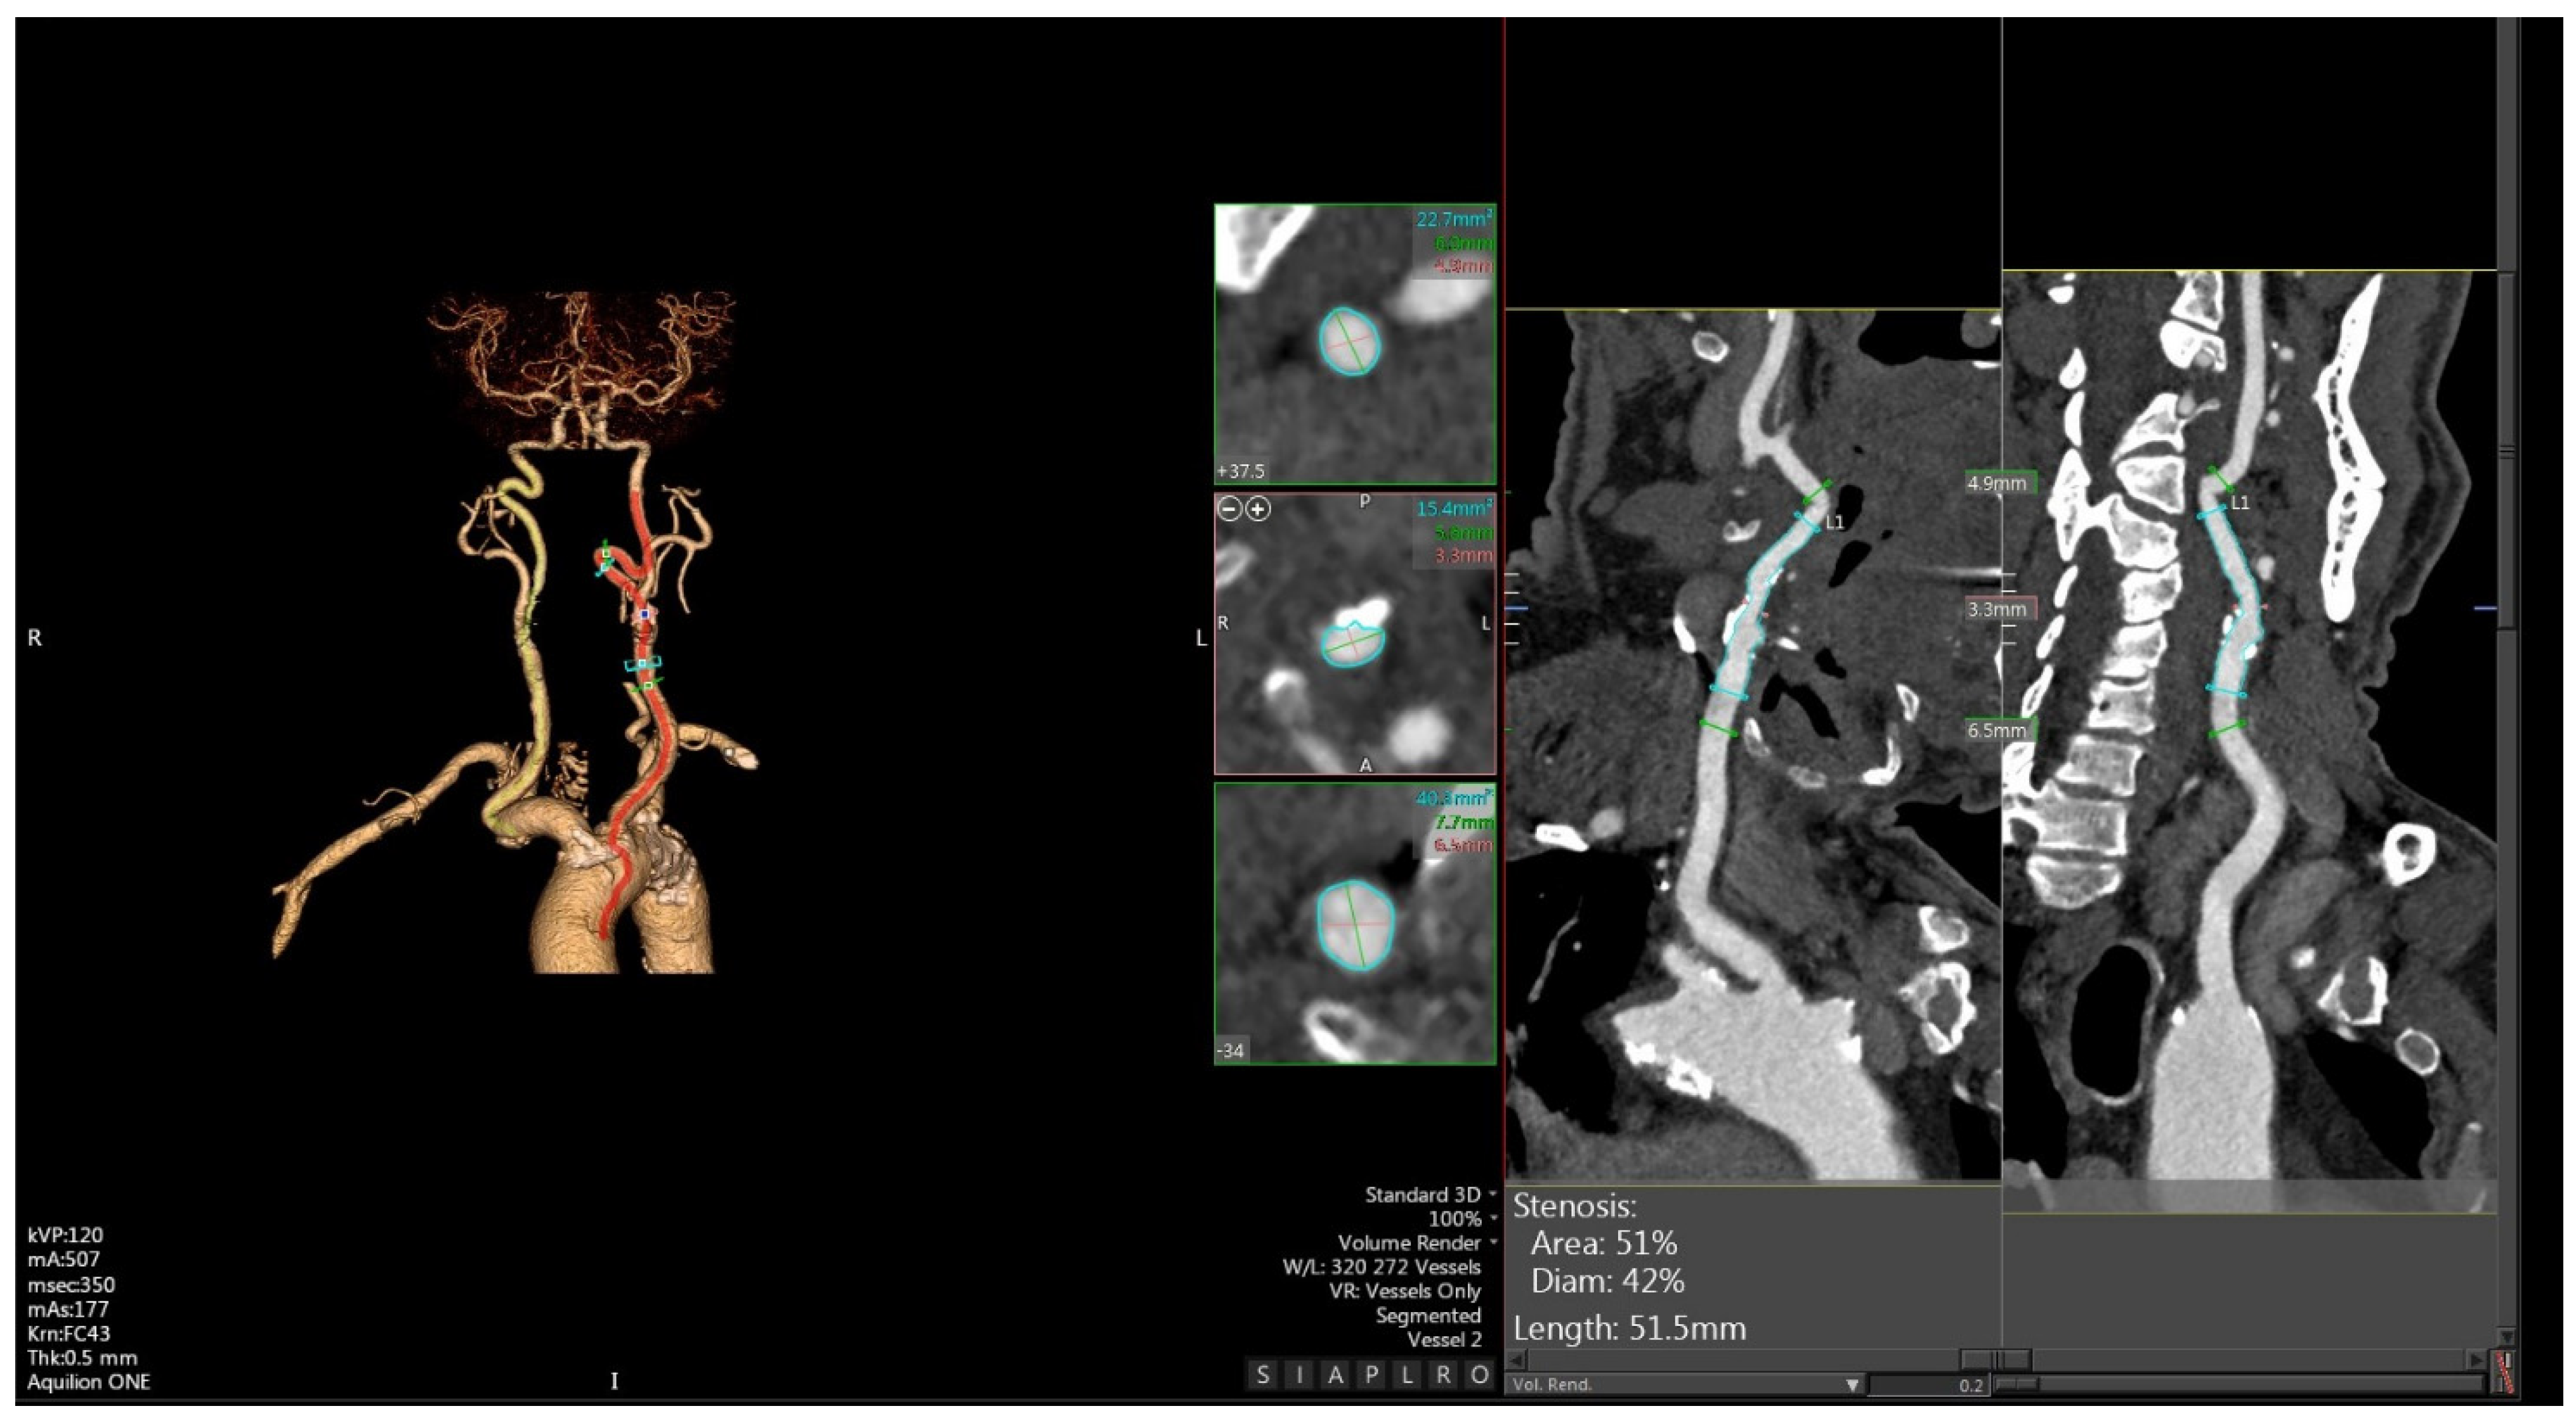

2. Multiparametric Ultrasound

3. CTA